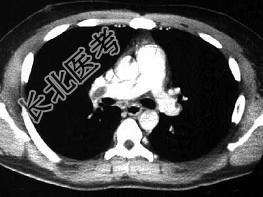

- 单项选择题男,28岁, 突发呼吸困难,结合影像图像, 选择最可能的诊断 ( )

A、右上肺大叶性肺炎

B、右上肺奇叶

C、右主肺动脉栓塞

D、右肺中央肺癌并右上肺不张,淋巴转移

E、右上肺小叶性肺炎